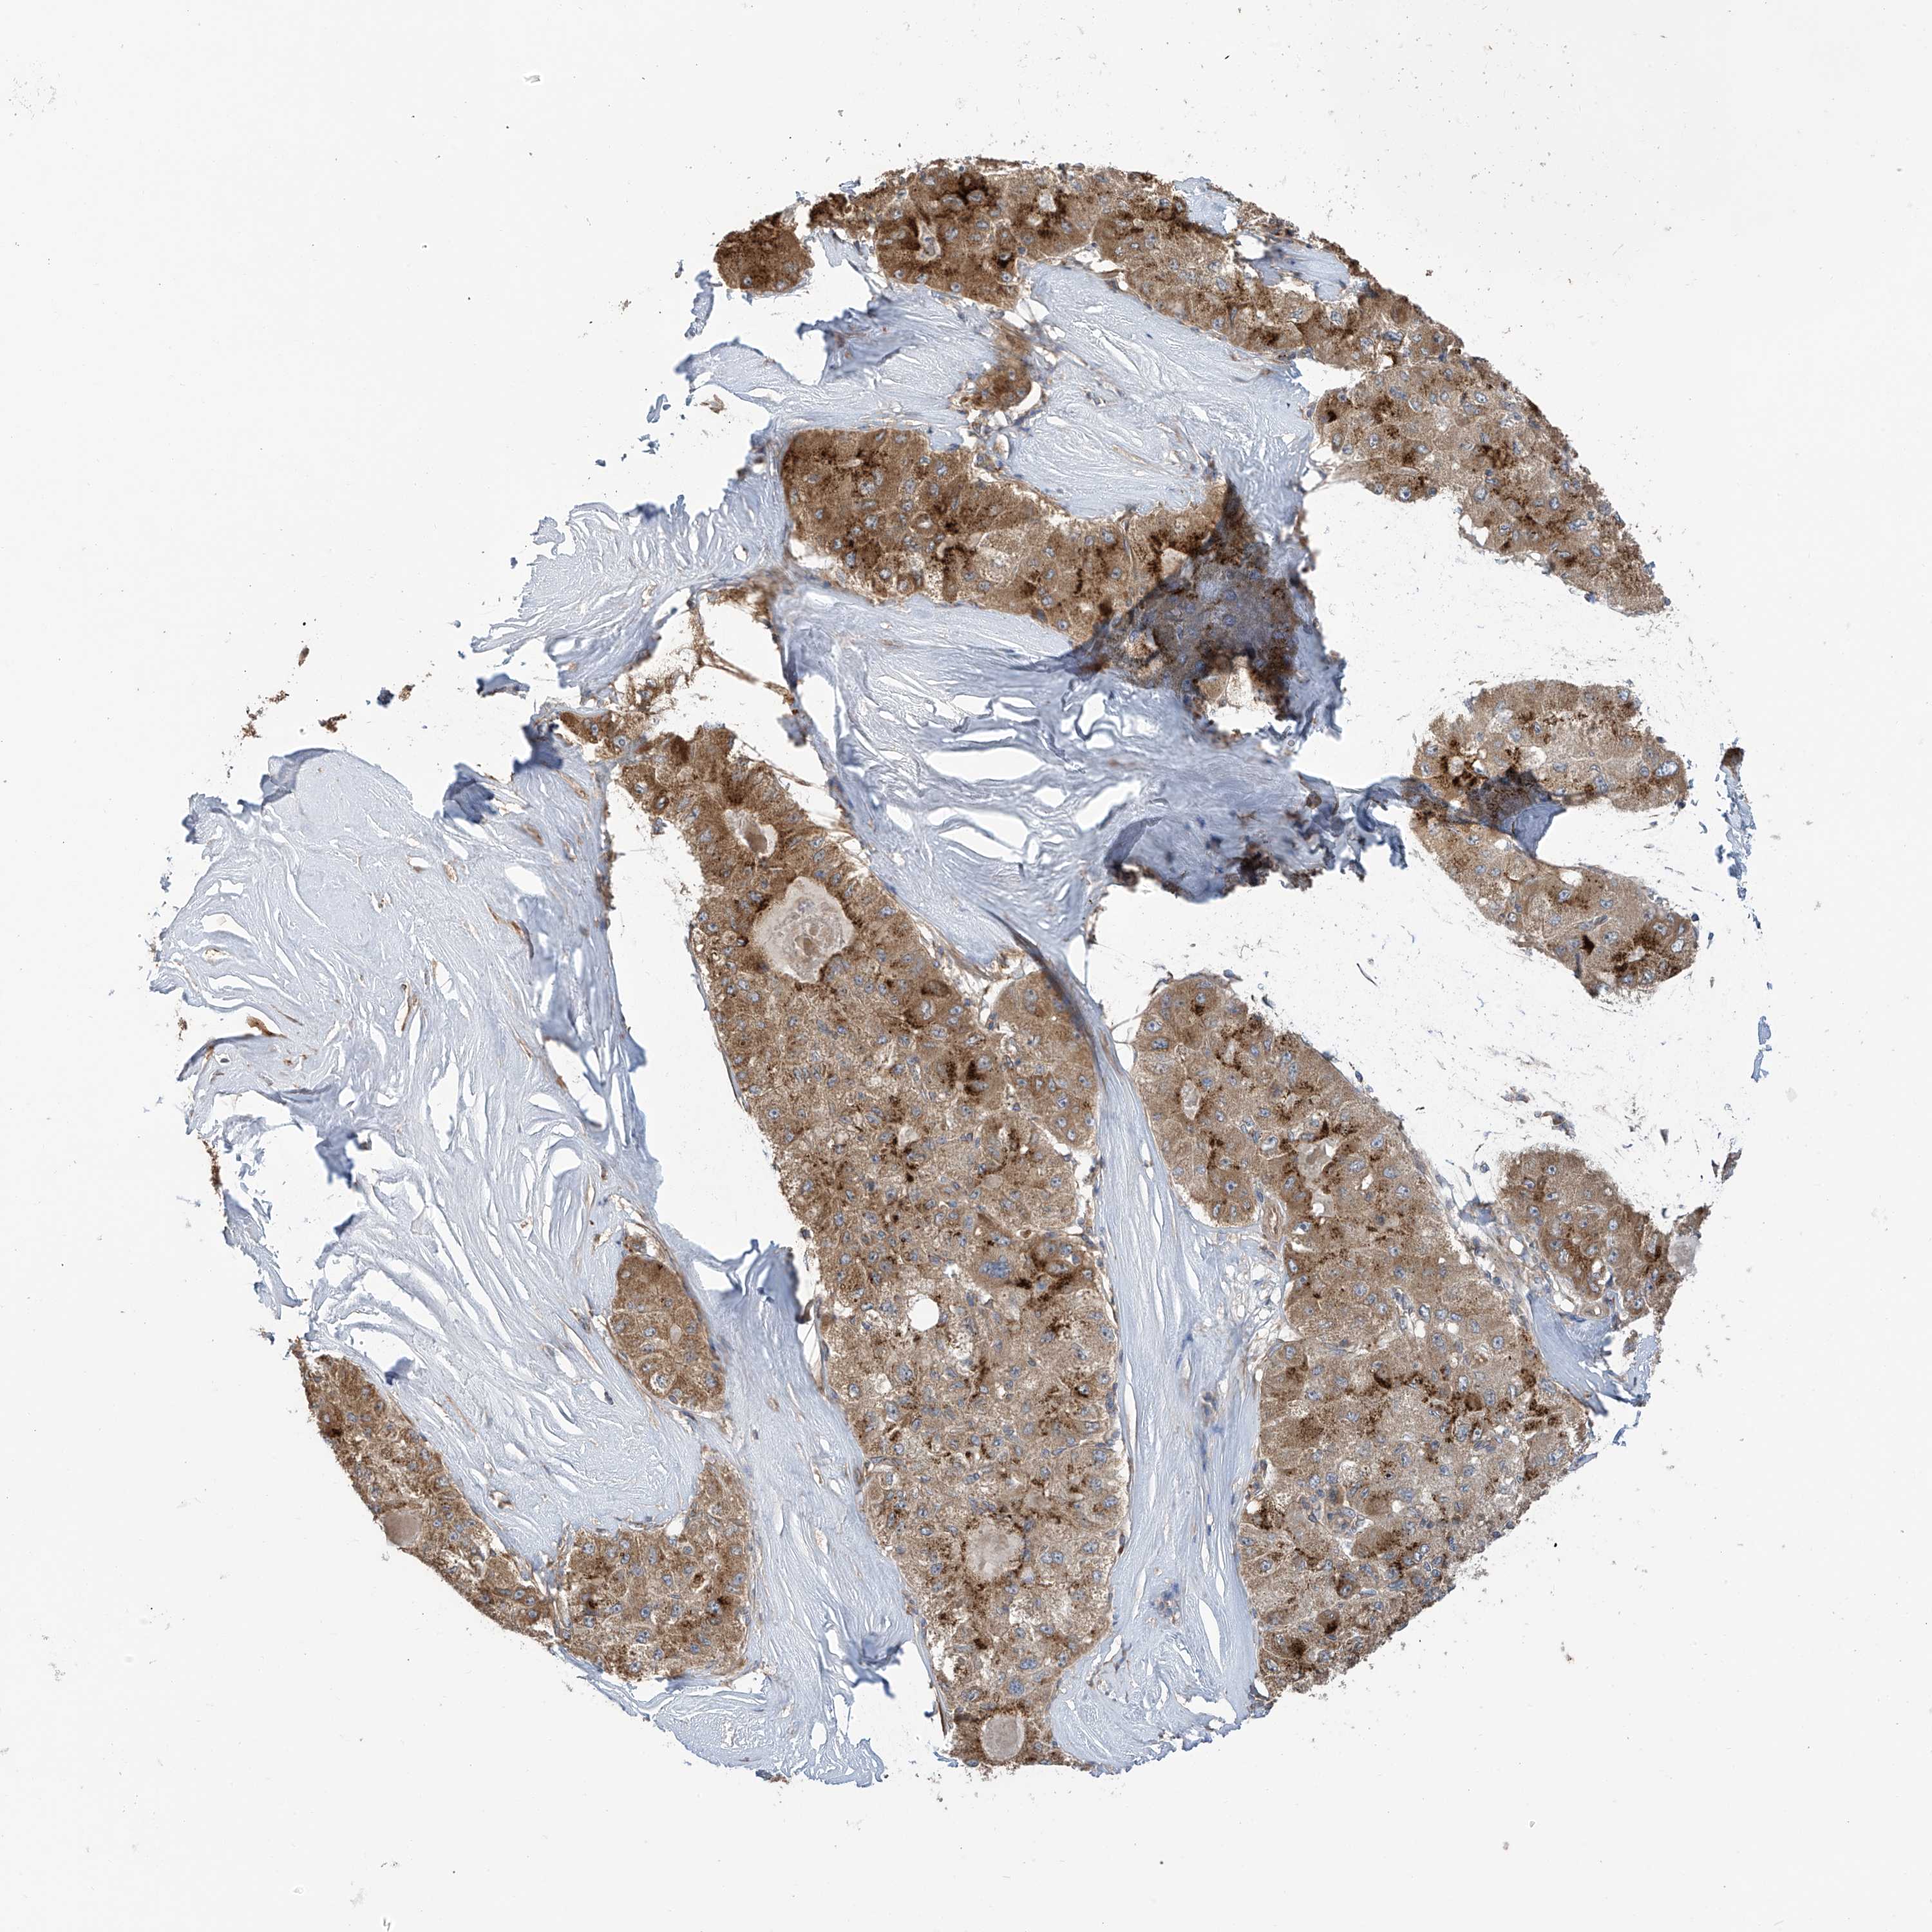

LIVER CANCER - Protein expressioni

A mouse-over function shows sample information and annotation data. Click on an image to view it in a full screen mode. Samples can be filtered based on level of antibody staining by selecting one or several of the following categories: high, medium, low and not detected. The assay and annotation is described here.

Note that samples used for immunohistochemistry by the Human Protein Atlas do not correspond to samples in the TCGA dataset.

Antibody stainingi

Antibody staining in the annotated cell types in the current human tissue is reported as not detected, low, medium, or high, based on conventional immunohistochemistry profiling in selected tissues. This score is based on the combination of the staining intensity and fraction of stained cells.

Each image is clickable and will lead to virtual microscopy that enables deeper exploration of all samples and also displays staining intensity scores, fraction scores and subcellular localization as well as patient and tissue information for each sample.

Antibody HPA034602

Antibody HPA034603

Antibody CAB033424

Staining

High

Medium

Low

Not detected

Intensity

Strong

Moderate

Weak

Negative

Quantity

>75%

75%-25%

<25%

None

Location

Nuclear

Cytoplasmic/membranous

Cytoplasmic/membranous,nuclear

Cholangiocarcinoma

Carcinoma, Hepatocellular, NOS